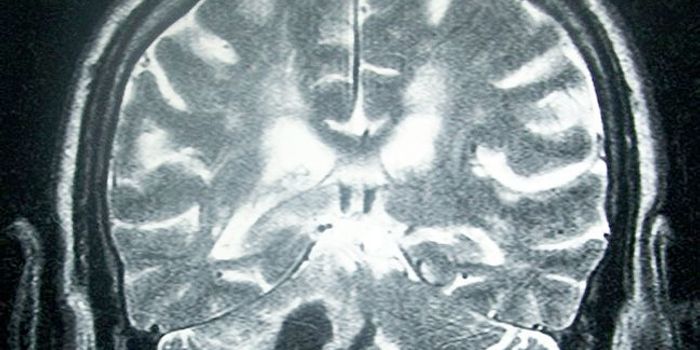

Read the latest articles about newly released neuroscience research and advances in experimental techniques. Topics include research news in neuroscience, neurology, psychology, brain science and cognitive sciences.